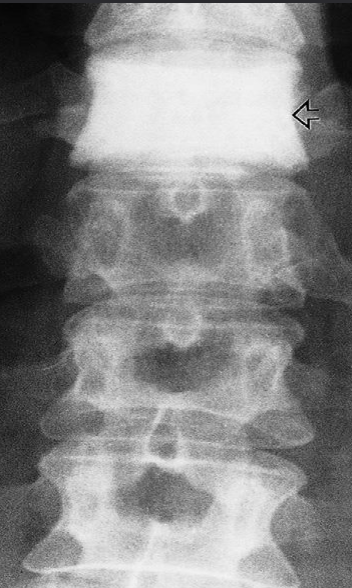

A. ONE radiological manifestation for marked abnormality.

Increased density and coarse trabeculae in the wider than the normal vertebral bodies (arrows)

B. Identify the most likely cause of the abnormal vertebrae shown Paget’s disease

Vertical striations are present in this normal-sized vertebra

B. Identify the most likely cause of the abnormal vertebrae shown Haemangioma